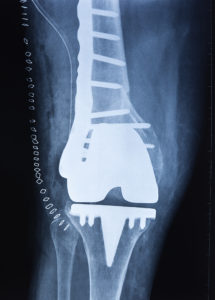

What is Total Joint Replacement Surgery? Total joint replacement is a surgical procedure involving the removal of damaged parts of a joint and the replacement of them with prosthetic pieces. The prosthetic pieces are designed to take on the functions of the damaged parts they replace, so the joint can function correctly once again. Joint replacement surgery is necessary when a joint is beyond natural healing and when other treatments fail to alleviate pain symptoms. It is a useful procedure [Read More]

The knee is the largest joint in the body and as such, undergoes a lot of stress. Whether it’s from wear and tear, an injury, carrying too much weight or degenerative joint disease, there is a good chance you or someone you know will be one of the more than 500,000 people each year who undergo a knee replacement procedure. If your knees are starting to bear the brunt of the pain and aren’t what they used to be, your orthopedist may recommend knee replacement surgery. Not to worry, though, these [Read More]